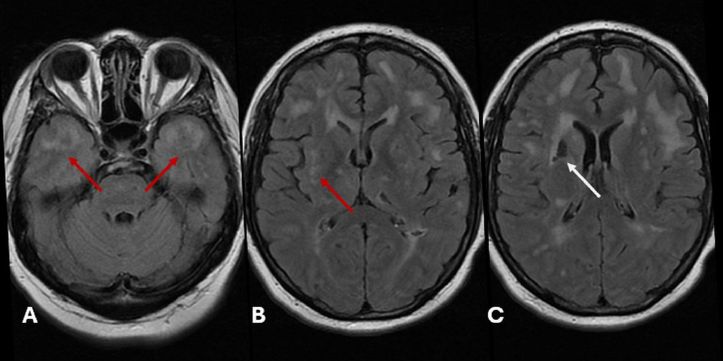

MRI revealed hyperintense lesions in the temporal poles and external capsules, plus a lacunar infarct in the gangliocapsular region—classic imaging features of CADASIL!